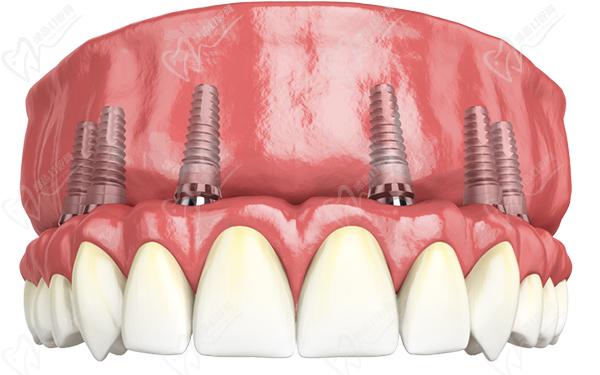

適合于:不差錢,想即刻微創(chuàng)修復(fù),當(dāng)天種牙當(dāng)天戴牙的患者。allon-6是上下頜各植入6顆種植體,恢 復(fù)滿口28顆牙齒的咀嚼功能。下半口牙齒同理,這樣全口種植牙就完成了。

西安滿口種植牙allon4/allon6即刻負(fù)重種植價格